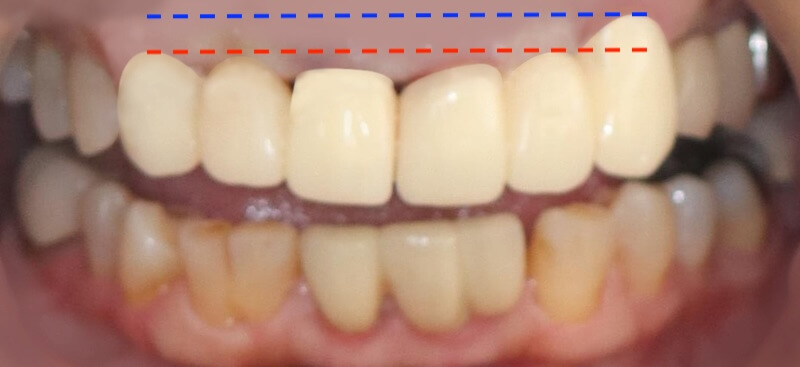

口內的檢查可以看到,在上顎前面六顆假牙,牙齦明顯腫起來。這可能來自兩個原因:

經過全口初步檢查以及X光片的檢查,我的診斷是全口中度慢性牙周病。治療牙周病過程中我會搭配顯微鏡和水雷射,也就是『顯微水雷射牙周病治療』。不過在牙周治療前,我們也要先把上述的兩個會加重牙周病的問題一併考量,治療才會有效果。

經過第一階段的療程後,我們持續追蹤 Ms.H 刷牙的情況,並且在大約兩個月後追蹤整體復原的進度,我們可以看到牙齦腫大的狀況明顯改善了許多,消腫以後產生了不少縫隙: